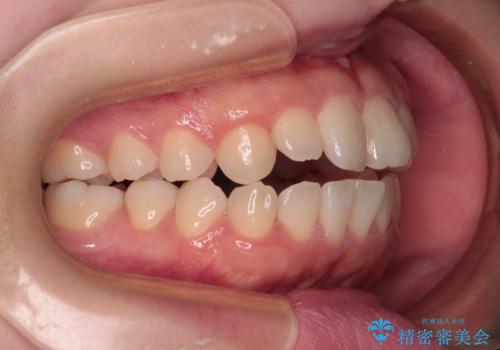

- 上下前歯の叢生と八重歯を気にして来院された患者様です。

前歯部叢生のスペースを獲得するため、上下顎左右小臼歯各1歯を抜歯することとしました。

歯列はきれいに整いますが、歯肉ラインは治療前の歯肉の位置を踏襲します。

特に八重歯であった歯は歯冠が長く見えますので、改善を希望される場合には、歯肉移植術を行う必要があります。